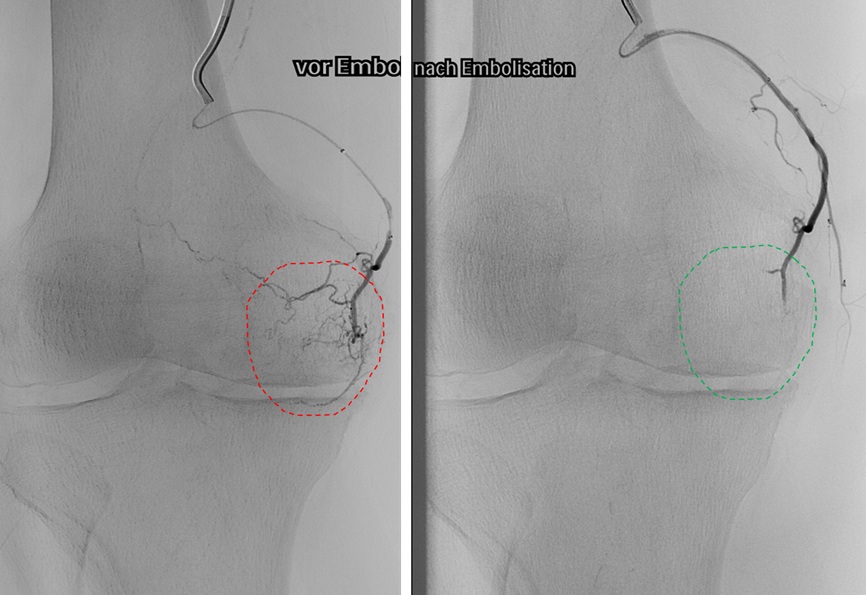

Ein weiterer Schwerpunkt ist die minimal-invasive Therapie von Gefäß- und Tumorerkrankungen. Dazu gehören rekanalisierende Eingriffe von Gefäßstenosen und –verschlüssen sowie embolisierende Verfahren bei onkologischen und vaskulären Erkrankungen.